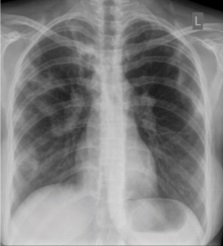

These are films that are completely normal, with no identifiable cardiothoracic or musculoskeletal abnormality.[citation needed]